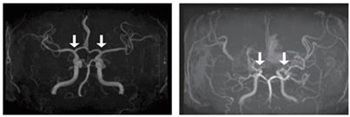

(사진 왼쪽부터 : 정상 및 모야모야병 환자의 뇌혈관)

모야모야병은 뇌로 혈액을 공급하는 혈관이 원인 없이 점차 좁아지는 만성 진행성 뇌혈관질환이다. 10세 전후 소아와 40세 전후 성인에서 주로 발병하며, 부작용으로는 뇌혈관이 막히거나 파열되는 허혈성·출혈성 뇌졸중이 있다.